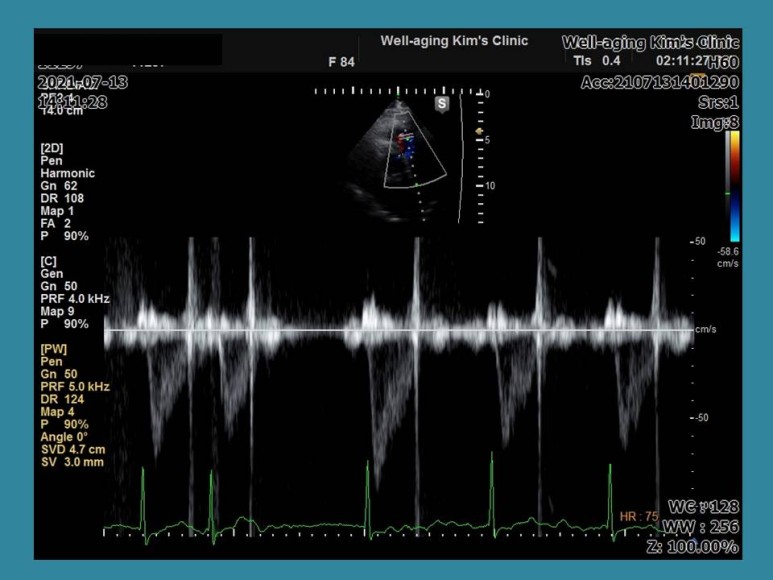

심장 초음파 검사를 실시하는 동일 안심 장박동수가 130회/분으로 갑자기 빨라지고 다시 정상 리듬으로 돌아왔다.가

이번에는 갑자기 심장박동기가 40~50회/분으로 느려지다가 중간에 동성정지 소견이 나타나고 불규칙한 맥박으로 바뀌는 상황이 3~4회 반복됐다.

이 경우 전형적인 빈맥-서맥증후군에 해당하며 환자가 증상은 없었지만 일단 수술을 중단하고 상급병원으로서 24시간 심전도 등의 검사가 필요하다는 것을 설명하고 이 환자는 인공심장박동기를 삽입할 수도 있는 경우이다.

이 환자의 경우도 외부 병원에서 찍은 심전도는 정상이었으나 심장 초음파 검사 중 우연히 부정맥이 발현돼 진단을 받은 경우다.